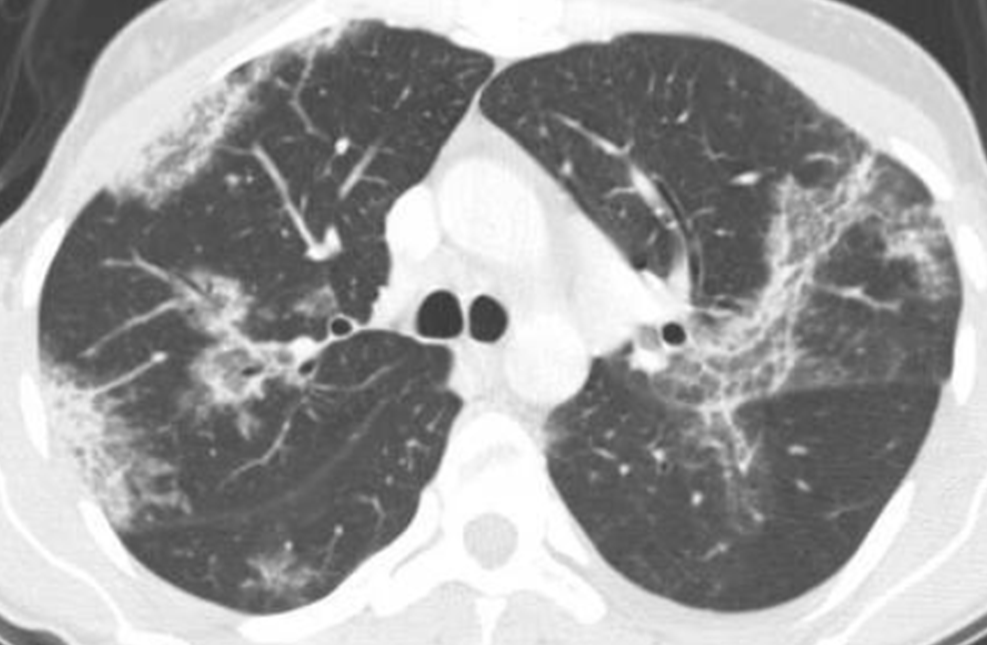

胸部CTでは、両側性のすりガラス影や浸潤影が主体で、その分布は非区域性・ランダムを基本としつつ、時に中枢優位、あるいは末梢優位となるなど多様性を示します。

(赤矢印:ランダム〜中枢優位のすりガラス影・浸潤影、青矢印:胸膜直下の非区域性浸潤影)